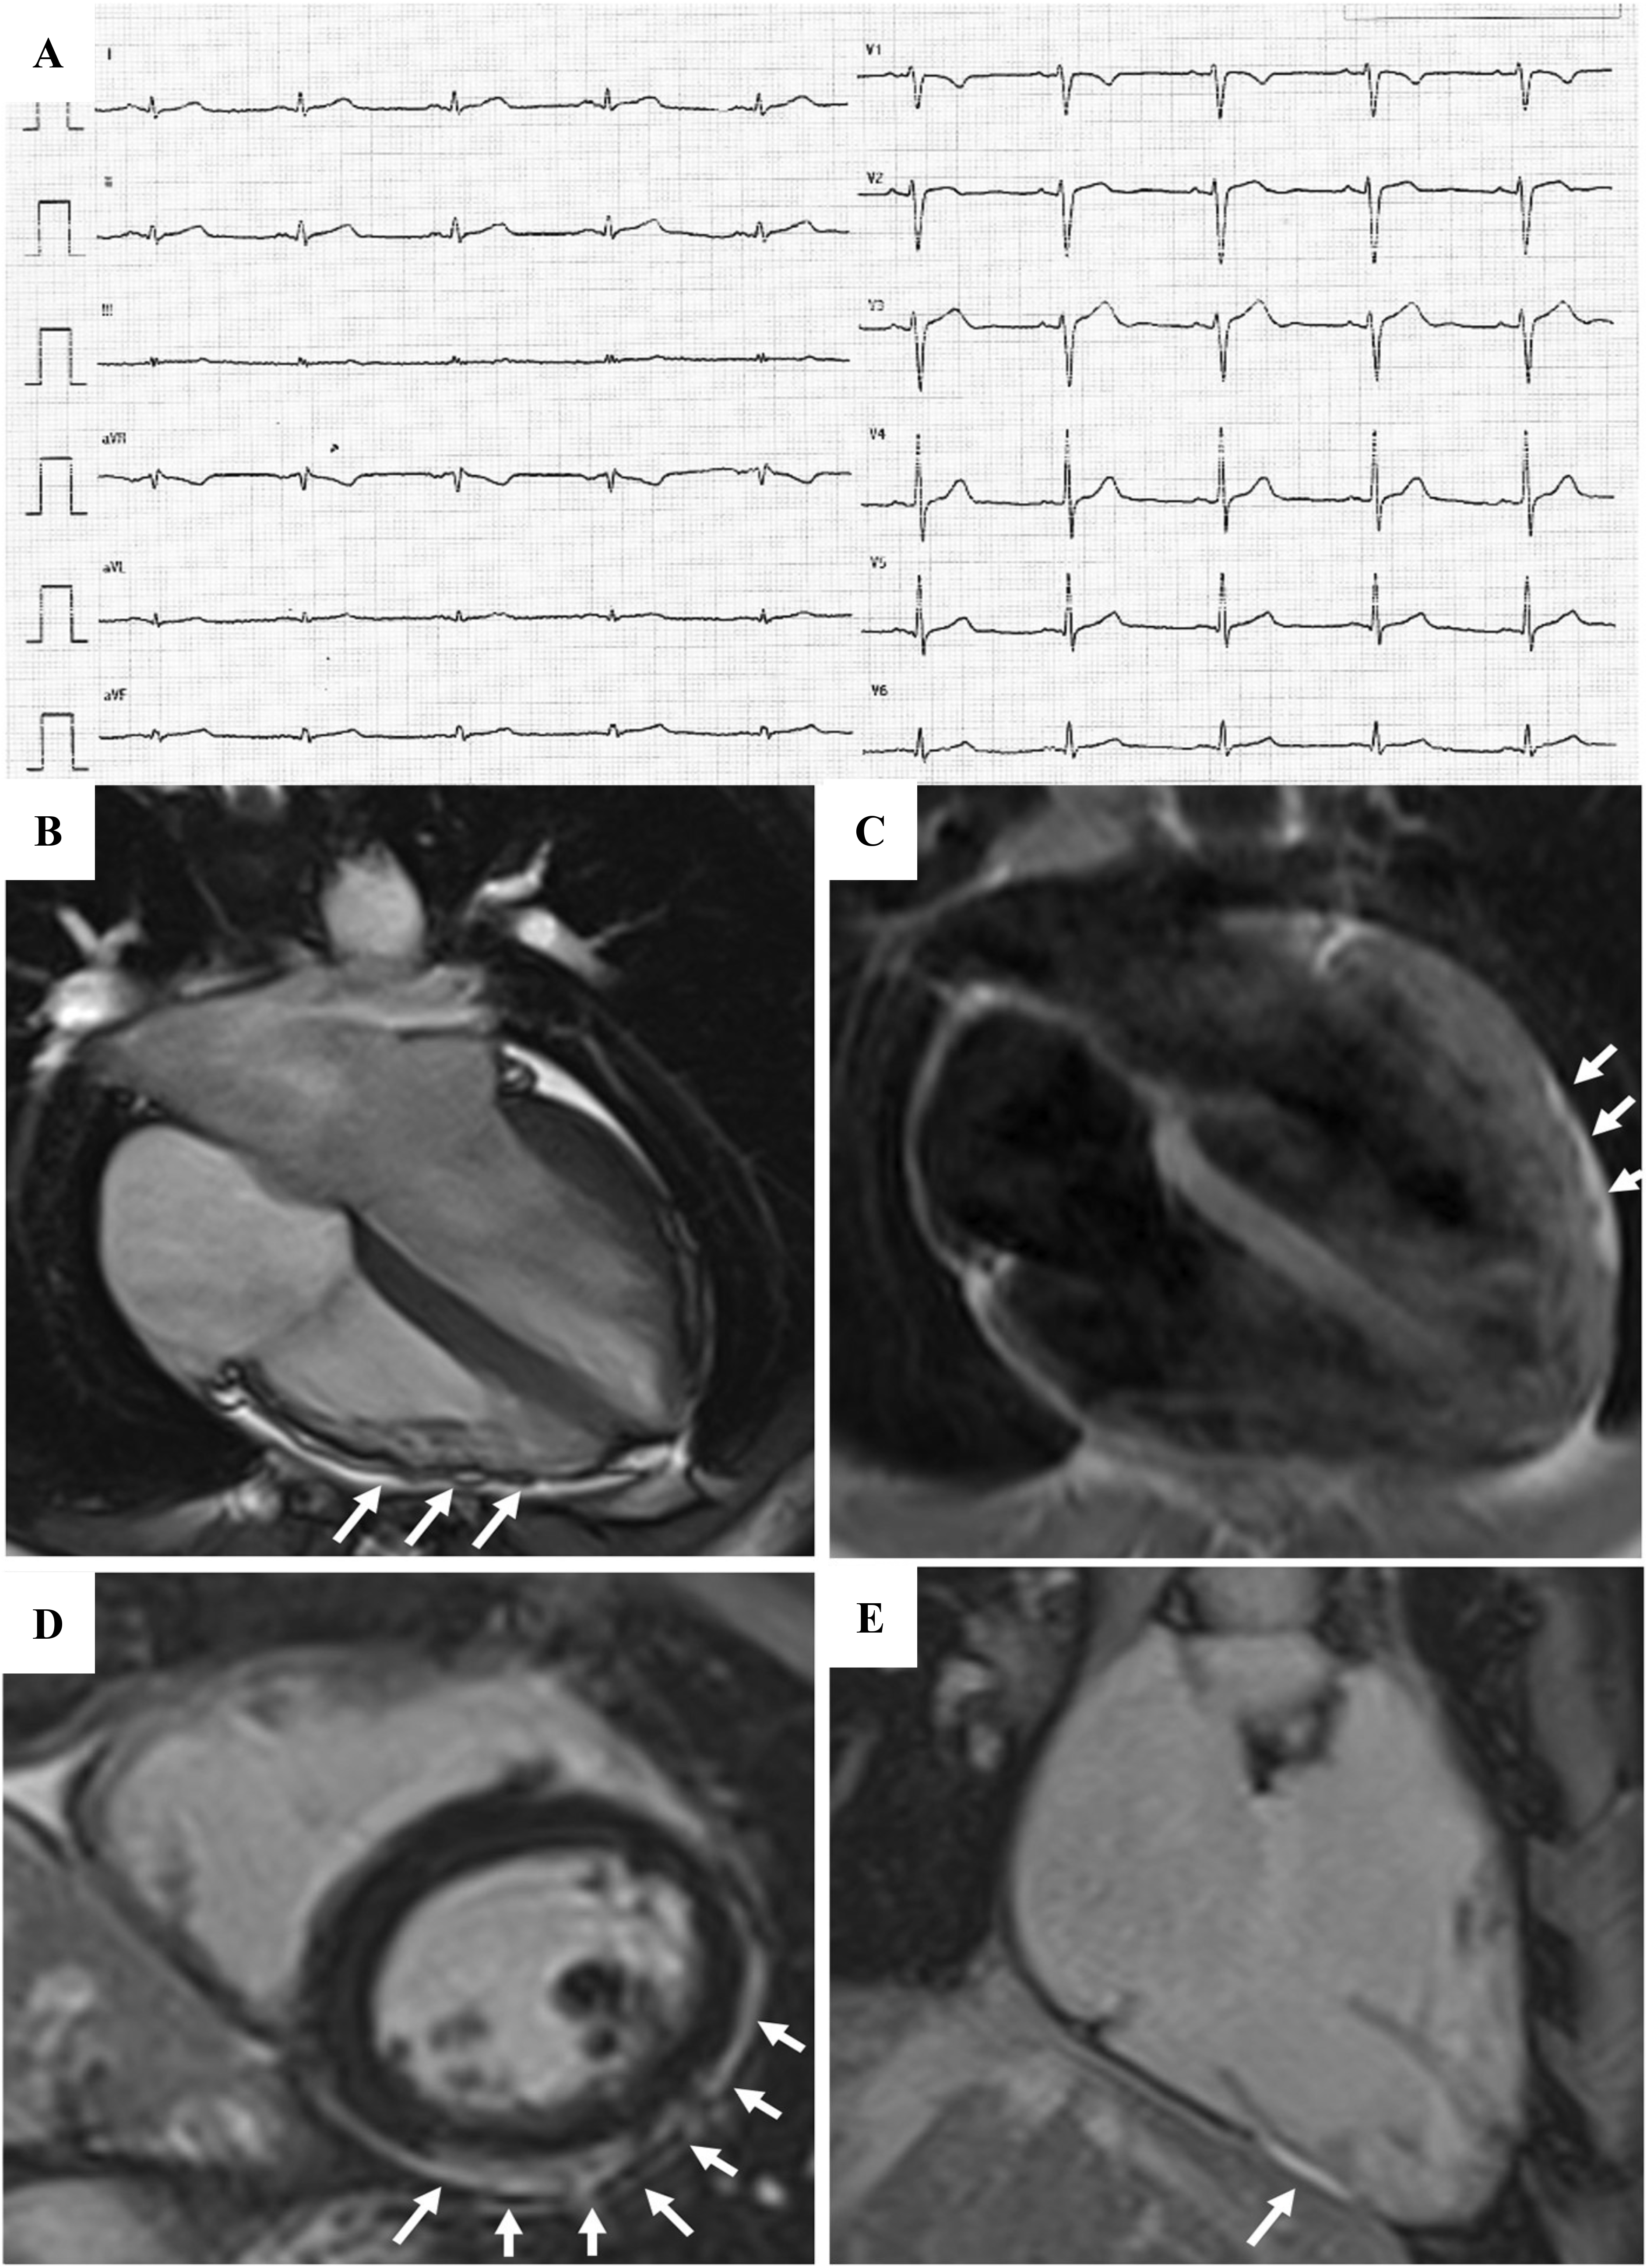

In the early stages of LV involvement, the typical non-ischemic distribution of fibro-fatty replacement sparing the subendocardial layer can explain the absence of wall motion abnormalities, dilatation, or dysfunction of the LV. Thereby, the absence of LV functional abnormalities on echo, cine-CMR or angiography cannot rule out LV involvement, and CE-CMR characterization plays a key role in detection of left-sided ACM [14, 16, 33, 34, 35, 36] (Fig. 4, Ref. [14]).

Fig. 4.

Fig. 4.Clinical and histopathological features of ALVC. Basal ECG and CMR findings in a patient who underwent cardiac transplantation because of ALVC related to a DSP gene mutation. Basal ECG revealed low QRS voltages in limb leads and flattened T-waves in infero-lateral leads (A). Post-contrast sequences on CMR (four-chamber view, B, and short-axis view, C) revealed subepicardial LGE involving the anterior septum and the whole LV free wall (“ring like” pattern) from basal to apical regions. Histology in LV inferolateral region demonstrated fibrofatty myocardial replacement in the subepicardial layer (D); a magnification of residual myocytes embedded within fibrous and fatty tissue (hematoxylin and eosin stain) (E). The diagnosis was “definite ALVC”. ALVC, arrhythmogenic left ventricular cardiomyopathy; CMR, cardiac magnetic resonance; DSP, desmoplakin gene; LGE, late gadolinium enhancement; LV, left ventricle. Adapted from Cipriani et al. [14].